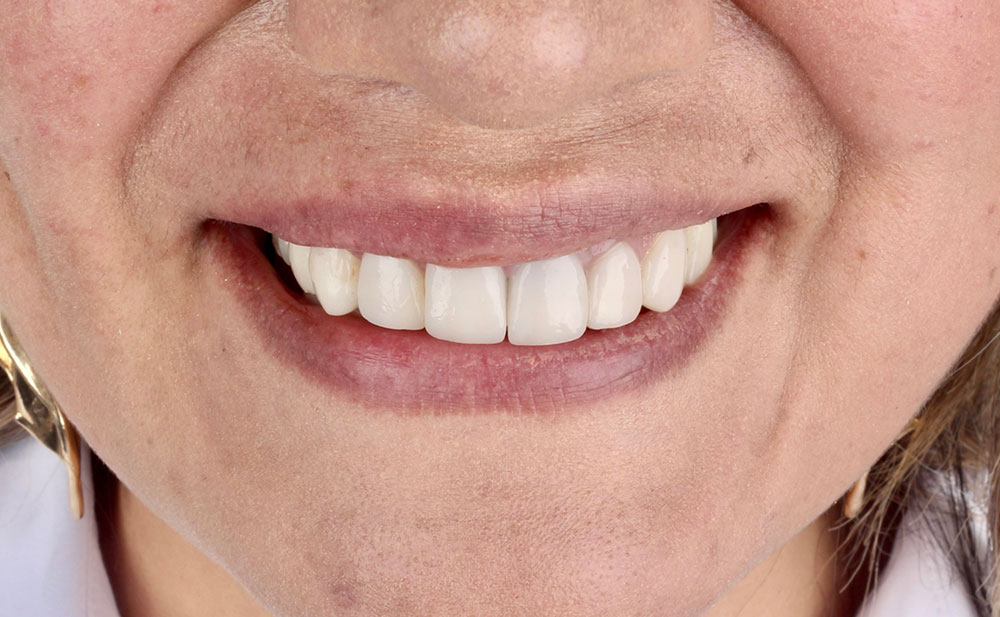

Después

Después

Después

Después

Después